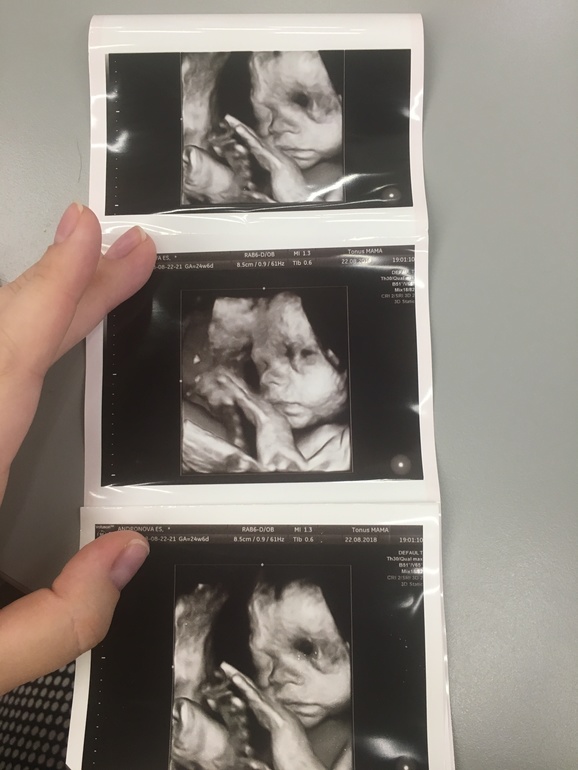

УЗИ 25-26 недель😊

Сходила на внеплановое УЗИ+допплер по своему желанию, поделюсь с вами😊 подкат+фото

Срок у меня 25+3 (на вчера) по последнему скринингу, по месячным не посчитать, потому что НМЦ, и О где-то на 55 дц была.

Малышка активная, но стеснительная, все время держит руки у личика. Все параметры примерно на 26 недель, а голова вперёд всего на 27 с лишним! Будет как её мама - чупачупс😅 я свою маму головой по всем направлениям разорвала🙈 щечки уже пухлые, хорошенькие, вес приблизительно 830г! Мне кажется, ноги коротковаты, тоже, видимо, не в папу😒 немного расстроилась...

Вот заключение УЗИ и первый хороший портрет симпатяги😊 спасибо, если дочитали!)